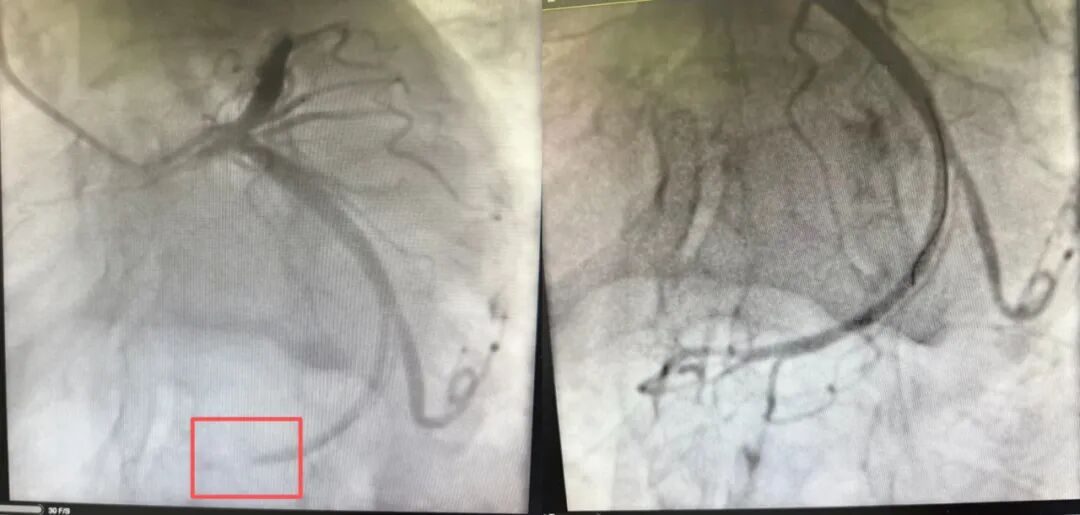

超声心动图揭开惊人真相:她的左心房,长了一个肿瘤,考虑为黏液瘤。更可怕的是,这颗肿瘤质地像果冻,松软易碎,碎裂的组织已经随着血液流窜,很可能已经堵住其心脏血管。当务之急是摸清其心脏血管情况,先将其从急性心梗的致命危险中抢救出来!浙江医院心血管内科副主任汤益民主任医师团队紧急实施冠脉造影,发现赵女士心脏三支主要血管之一回旋支远端完全闭塞,介入治疗中,他们顺利将堵塞血管的“血栓样”物质取出,患者血流恢复通畅。

血管开通前(左)后(右)图片由医院提供